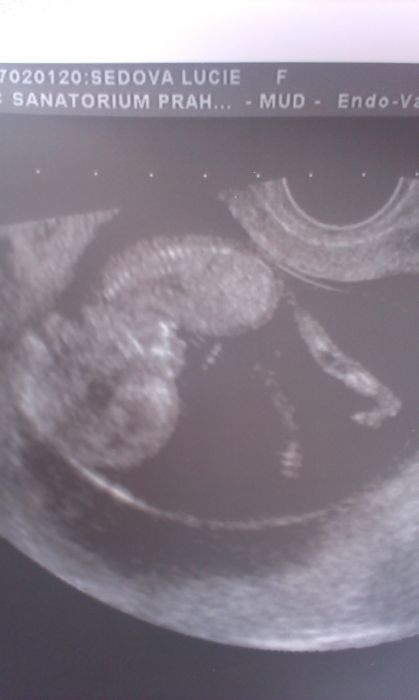

Aha tak tojá podle toho uz byla 12+4 to znamená o deset dní mín jak PM. a ukázala mi ho tam ,ale prý to může být pupečník,uvidíme 20.8., ale i když se to krásně vrtělo byla fotka tak doložím

Tady je jen 2d foto mimiska. Teď me viděla kamarádka po 10 dnech a prej sem nakynula:-(